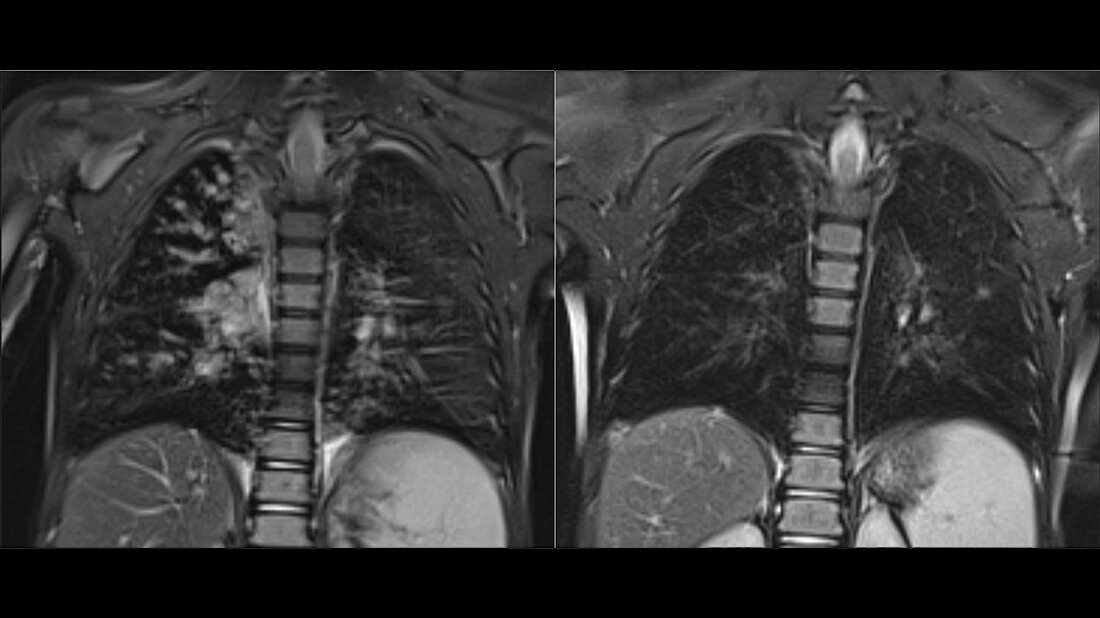

Anhand der Daten von 107 Kindern, die an Mukoviszidose leiden, konnten die Forschenden den deutlichen Nutzen zeigen. Innerhalb eines einjährigen Untersuchungszeitraums der Kinder zeigte sich, dass die Dreifachtherapie nicht nur die Schwere der Symptome reduziert, sondern auch das Voranschreiten der Erkrankung stoppt. Bei den meisten Kindern übertrafen die Werte sogar die der Erwachsenen und sie erlangten eine normale Lungenfunktion.

Momentan wird eine ähnliche Studie für Kinder zwischen zwei und fünf Jahren durchgeführt. Die Hoffnung ist, dass ein früher Start der Behandlung die Entwicklung schwerwiegender Symptome und strukturelle Veränderungen der Lunge verhindern kann. Zudem untersuchen sie, ob sich die Basistherapie der Symptome durch die Dreifachtherapie reduzieren lässt.